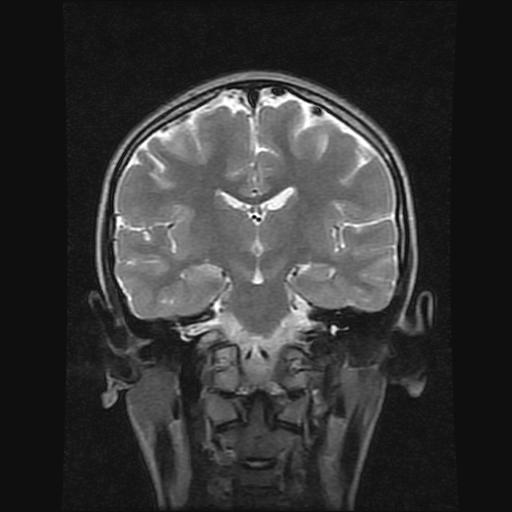

9岁女孩,三岁时诊断为癫痫,一直服丙戊酸钠,现患者一般情况良好,家长复查核磁片,看能否停药..

巨脑回